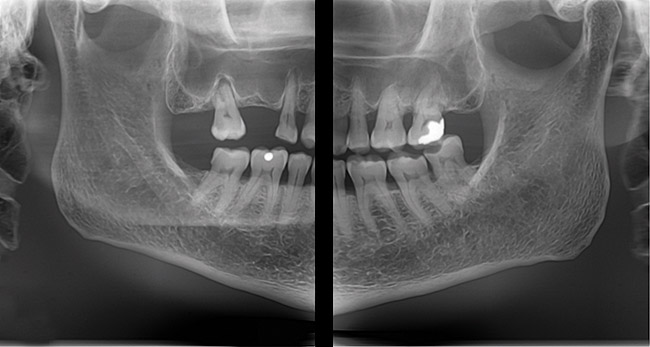

Digital images captured by a sensor are displayed on the monitor in shades of gray (Figure 2). The grayscale displayed by the monitor is comprised of 256 distinct visible shades of gray even though some systems can contain up to 64,000 values.15 The human eye can only distinguish up to 32 shades of gray; this fact will be important later when the concept of image processing is presented. Each pixel in the digital image has a number ranging from 0 to 255. The radiation is registered when the sensor captures it. Maximum radiation is zero on this scale (pure black) and no radiation penetration (total radiopacity) is 255 (pure white).15 This radiation intensity is sent to the computer and stored. Dental professionals rely on the contrast of a radiograph to be able to detect disease processes; the longer the scale of contrast in the image, the easier it is to make a diagnosis. With the ability to enhance gray scales using the software that accompanies the sensor in an x-ray digital imaging system, a clinician may be better able to diagnose even subtle changes that may have been missed previously with conventional films.16-18

Figure 2